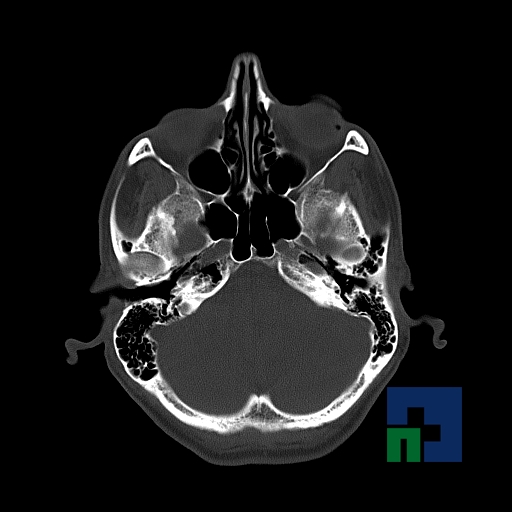

În cazul traumatismelor cranio-cerebrale:

- Diagnosticul edemului cerebral, a contuziei cerebrale, a leziunilor axonale difuze edematoase/hemoragice, a dilacerării cerebrale, a hematomului intraparenchimatos posttraumatic, a hematoamelor subdurale/extradurale (acute, subacute, cronice), a hemoragiei intraventriculare, a hemoragiei subarahnoidiene

- Diagnosticul traumatismelor de bază de craniu

- Diagnosticul fracturilor:

-

- Unice

- Multiple

- Cu înfundare

- Complexe cranio-sinusale

- Complexe cranio-etmoidale

- Complexe cranio-orbitare

- Complexe cranio-faciale